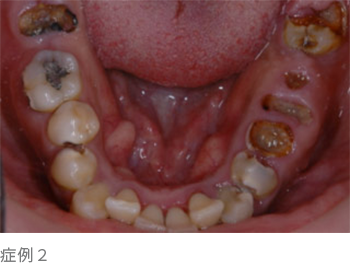

ほとんどの方が大切な歯を失う要因として虫歯を連想されると思いますが、虫歯は宿主、細菌、時間、糖質摂取等の因子が全て揃うと発症し、"歯そのもの"が破壊される病気(写真下)です。

歯周病は細菌性バイオフィルム、宿主生体防御機構の低下、生活習慣、時間などこれら1、2つの因子が揃うだけで発症する"歯を支えている周りの組織(歯周組織)"に起こる病気で、虫歯と同等以上に歯周病(歯槽膿漏)で歯を失ってしまう方が多いのです。